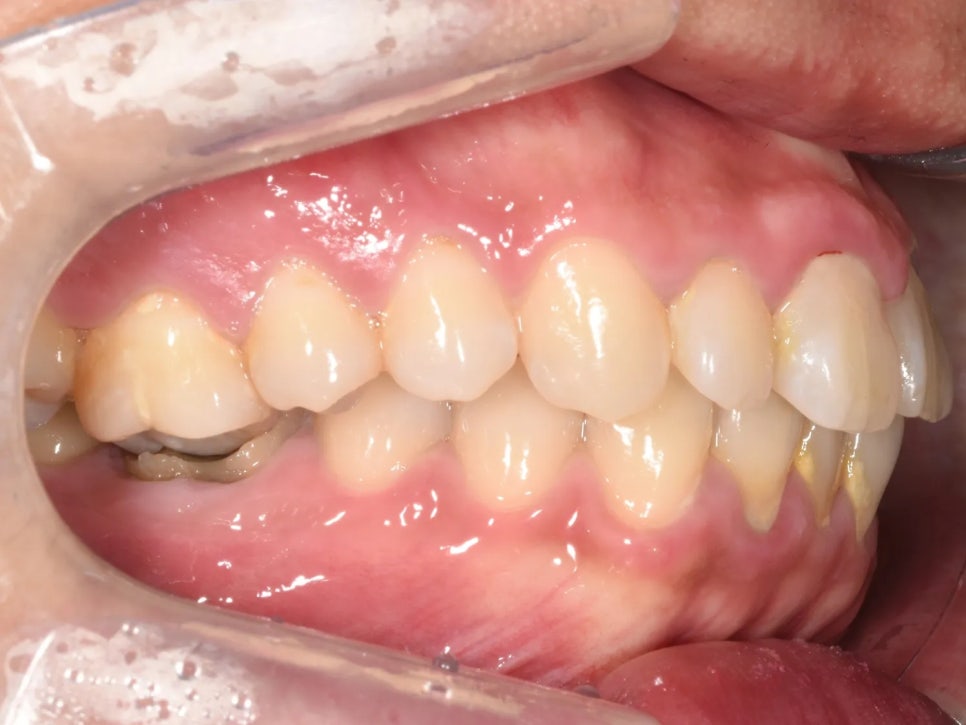

추가적으로, 아래쪽 오른쪽 첫째 어금니에는 심한 충치가 있었고, 반대쪽(왼쪽) 아래 두 번째 작은어금니는 이미 빠진 상태(결손)였습니다. 충치로 인해 치아 높이가 낮아지면서 위 어금니가 더 빨리 정출되었고, 결손 부위에서는 인접 치아가 빈 공간 쪽으로 쓰러져 있었습니다. 아래 사진을 보시면 이 모든 이유 때문에 결국 환자분이 아래턱을 틀어 물고 있는 것도 확인해보실 수 있습니다.

아래턱을 약간 왼쪽(→)으로 물고 있는 것이 보이십니까?